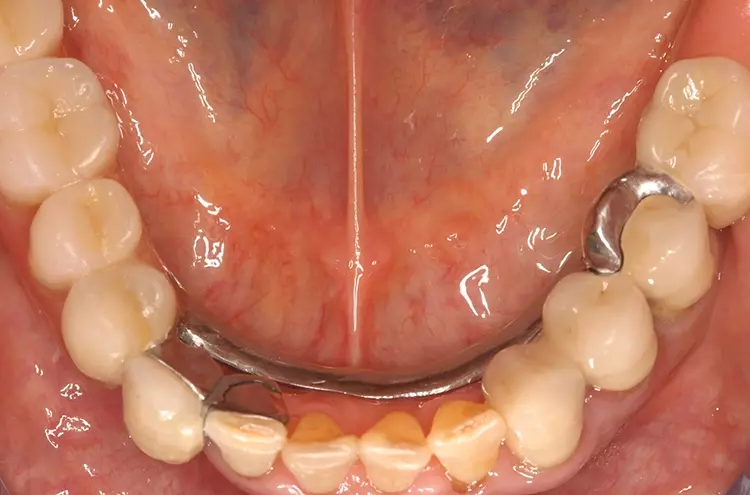

Als relative Kontraindikation sind karies- und restaurationsfreie Pfeilerzähne mit zervikalen keilförmigen Defekten über 1 mm Tiefe zu nennen, da diese zu einer erhöhten Frakturgefahr des Pfeilerzahnes bei Belastung führen. Adhäsivattachments können zur Reparatur vorhandener Doppelkronen- oder Geschiebearbeiten verwendet werden, sofern der verbliebene Nachbarzahn einer verloren gegangenen Doppelkrone karies- und restaurationsfrei ist. Die Matrize wird in diesem Fall in die ausgeschliffene Doppelkrone oder in die Geschiebekrone des verlorenen Pfeilerzahns eingeklebt (Abb. 1 bis 4).